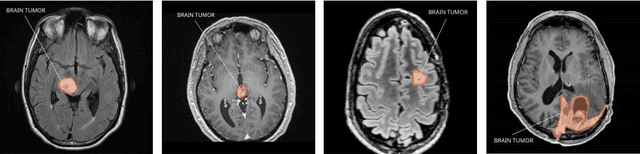

Abstract:The growth of abnormal cells in the brain's tissue causes brain tumors. Brain tumors are considered one of the most dangerous disorders in children and adults. It develops quickly, and the patient's survival prospects are slim if not appropriately treated. Proper treatment planning and precise diagnoses are essential to improving a patient's life expectancy. Brain tumors are mainly diagnosed using magnetic resonance imaging (MRI). As part of a convolution neural network (CNN)-based illustration, an architecture containing five convolution layers, five max-pooling layers, a Flatten layer, and two dense layers has been proposed for detecting brain tumors from MRI images. The proposed model includes an automatic feature extractor, modified hidden layer architecture, and activation function. Several test cases were performed, and the proposed model achieved 98.6% accuracy and 97.8% precision score with a low cross-entropy rate. Compared with other approaches such as adjacent feature propagation network (AFPNet), mask region-based CNN (mask RCNN), YOLOv5, and Fourier CNN (FCNN), the proposed model has performed better in detecting brain tumors.